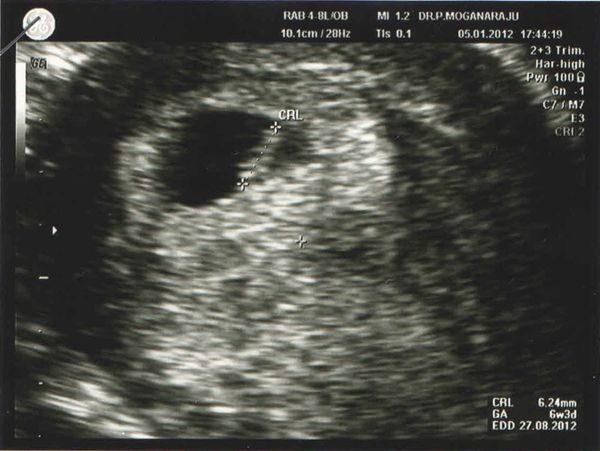

5/1/2012 第一次產檢

剛開始找BB的時候真的超緊張的, 隱隱約約看見胎囊...

過後醫生zoom大再zoom大 (還zoom大過頭) 問我們看見心跳嗎??

我看見monitor期中一部份隱隱約約的在閃爍著, 大概知道在哪裡囉!!

但是醫生擔心我們看不見, 換了個有顏色的mode, 就立刻清楚的看見可愛的心跳囉!!

醫生說以BB的長度大概只有六周多, 現階段還小, 不用擔心BB應該有七周的了!

BB的第一張照片!!